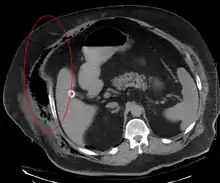

التشخيص المبكر صعب لأن المرض غالبا ما يبدو في وقت مبكر مثل التهاب الجلد السطحي البسيط.[2] في حين أن عددا من الطرائق المخبرية والتصويرية يمكن أن تثير الشك لالتهاب اللفافة الناخر، المعيار الذهبي لتشخيص واستكشاف جراحي في وضع مرتفع. عندما تكون في شك، يمكن إجراء شق صغيرة "ثقب المفتاح" في الأنسجة المتضررة، وإذا كان الإصبع يفصل بسهولة الأنسجة على طول الخط اللفافي، فان التشخيص مؤكد ويجب إجراء التنضير واسعة النطاق.[6]

المقطعي المحوسب (الأشعة المقطعية) على وشك الكشف عن حوالي 80٪ من الحالات بينما قد يتمكن التصوير بالرنين المغناطيسي من الالتقاط أكثر قليلا.[16]